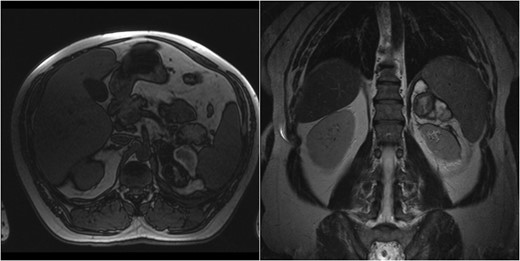

Case 1 follow-up MRI showing almost complete resolution of the hematoma and absence of underlying adrenal lesion.

Spontaneous AH, represents a rare condition [1, 7–9]. It includes cases associated with adrenal masses [4], pregnancy [5] (due to cortex hypertrophy and hyperplasia) and idiopathic cases [6]. Trauma, resulting in adrenal vein thrombosis, hypertensive crisis and corticotropin therapy, have been reported [1]. Risk factors in this report included hypertension in the first case, while the second patient had no known predisposing factors other than antiplatelet medication. This association has been previously reported [4]. Patients with AH, present with abdominal pain [1, 4–6]. However, the majority present insidiously [1]. Diagnosis is established by CT or MRI [4]. An adrenal hematoma has a heterogeneous, high density appearance on CT, while in the acute setting, the presence of an underlying adrenal mass cannot be excluded [4]. MRI is the most accurate imaging technique and differentiates subacute from chronic hemorrhage [4]. In both our cases, diagnosis was made with CT, while MRI confirmed hematoma resolution and absence of mass.